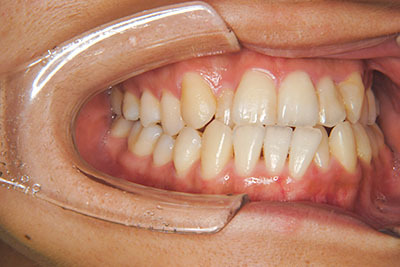

おとなの方でも矯正治療をあきらめないでください!

いくら歯が動き易くとも、本人がやる気でなければ効果は出ませんし、むし歯発生のリスクも高まります。おとなの方は顎の成長が終わっているため、治療の計画が立てやすいとも言えます。「もう大人だから…」とあきらめず、一度ご相談ください。